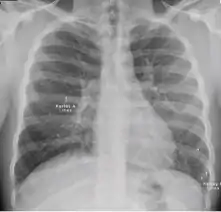

Normal findings

These are films that are completely normal, with no identifiable cardiothoracic or musculoskeletal abnormality.